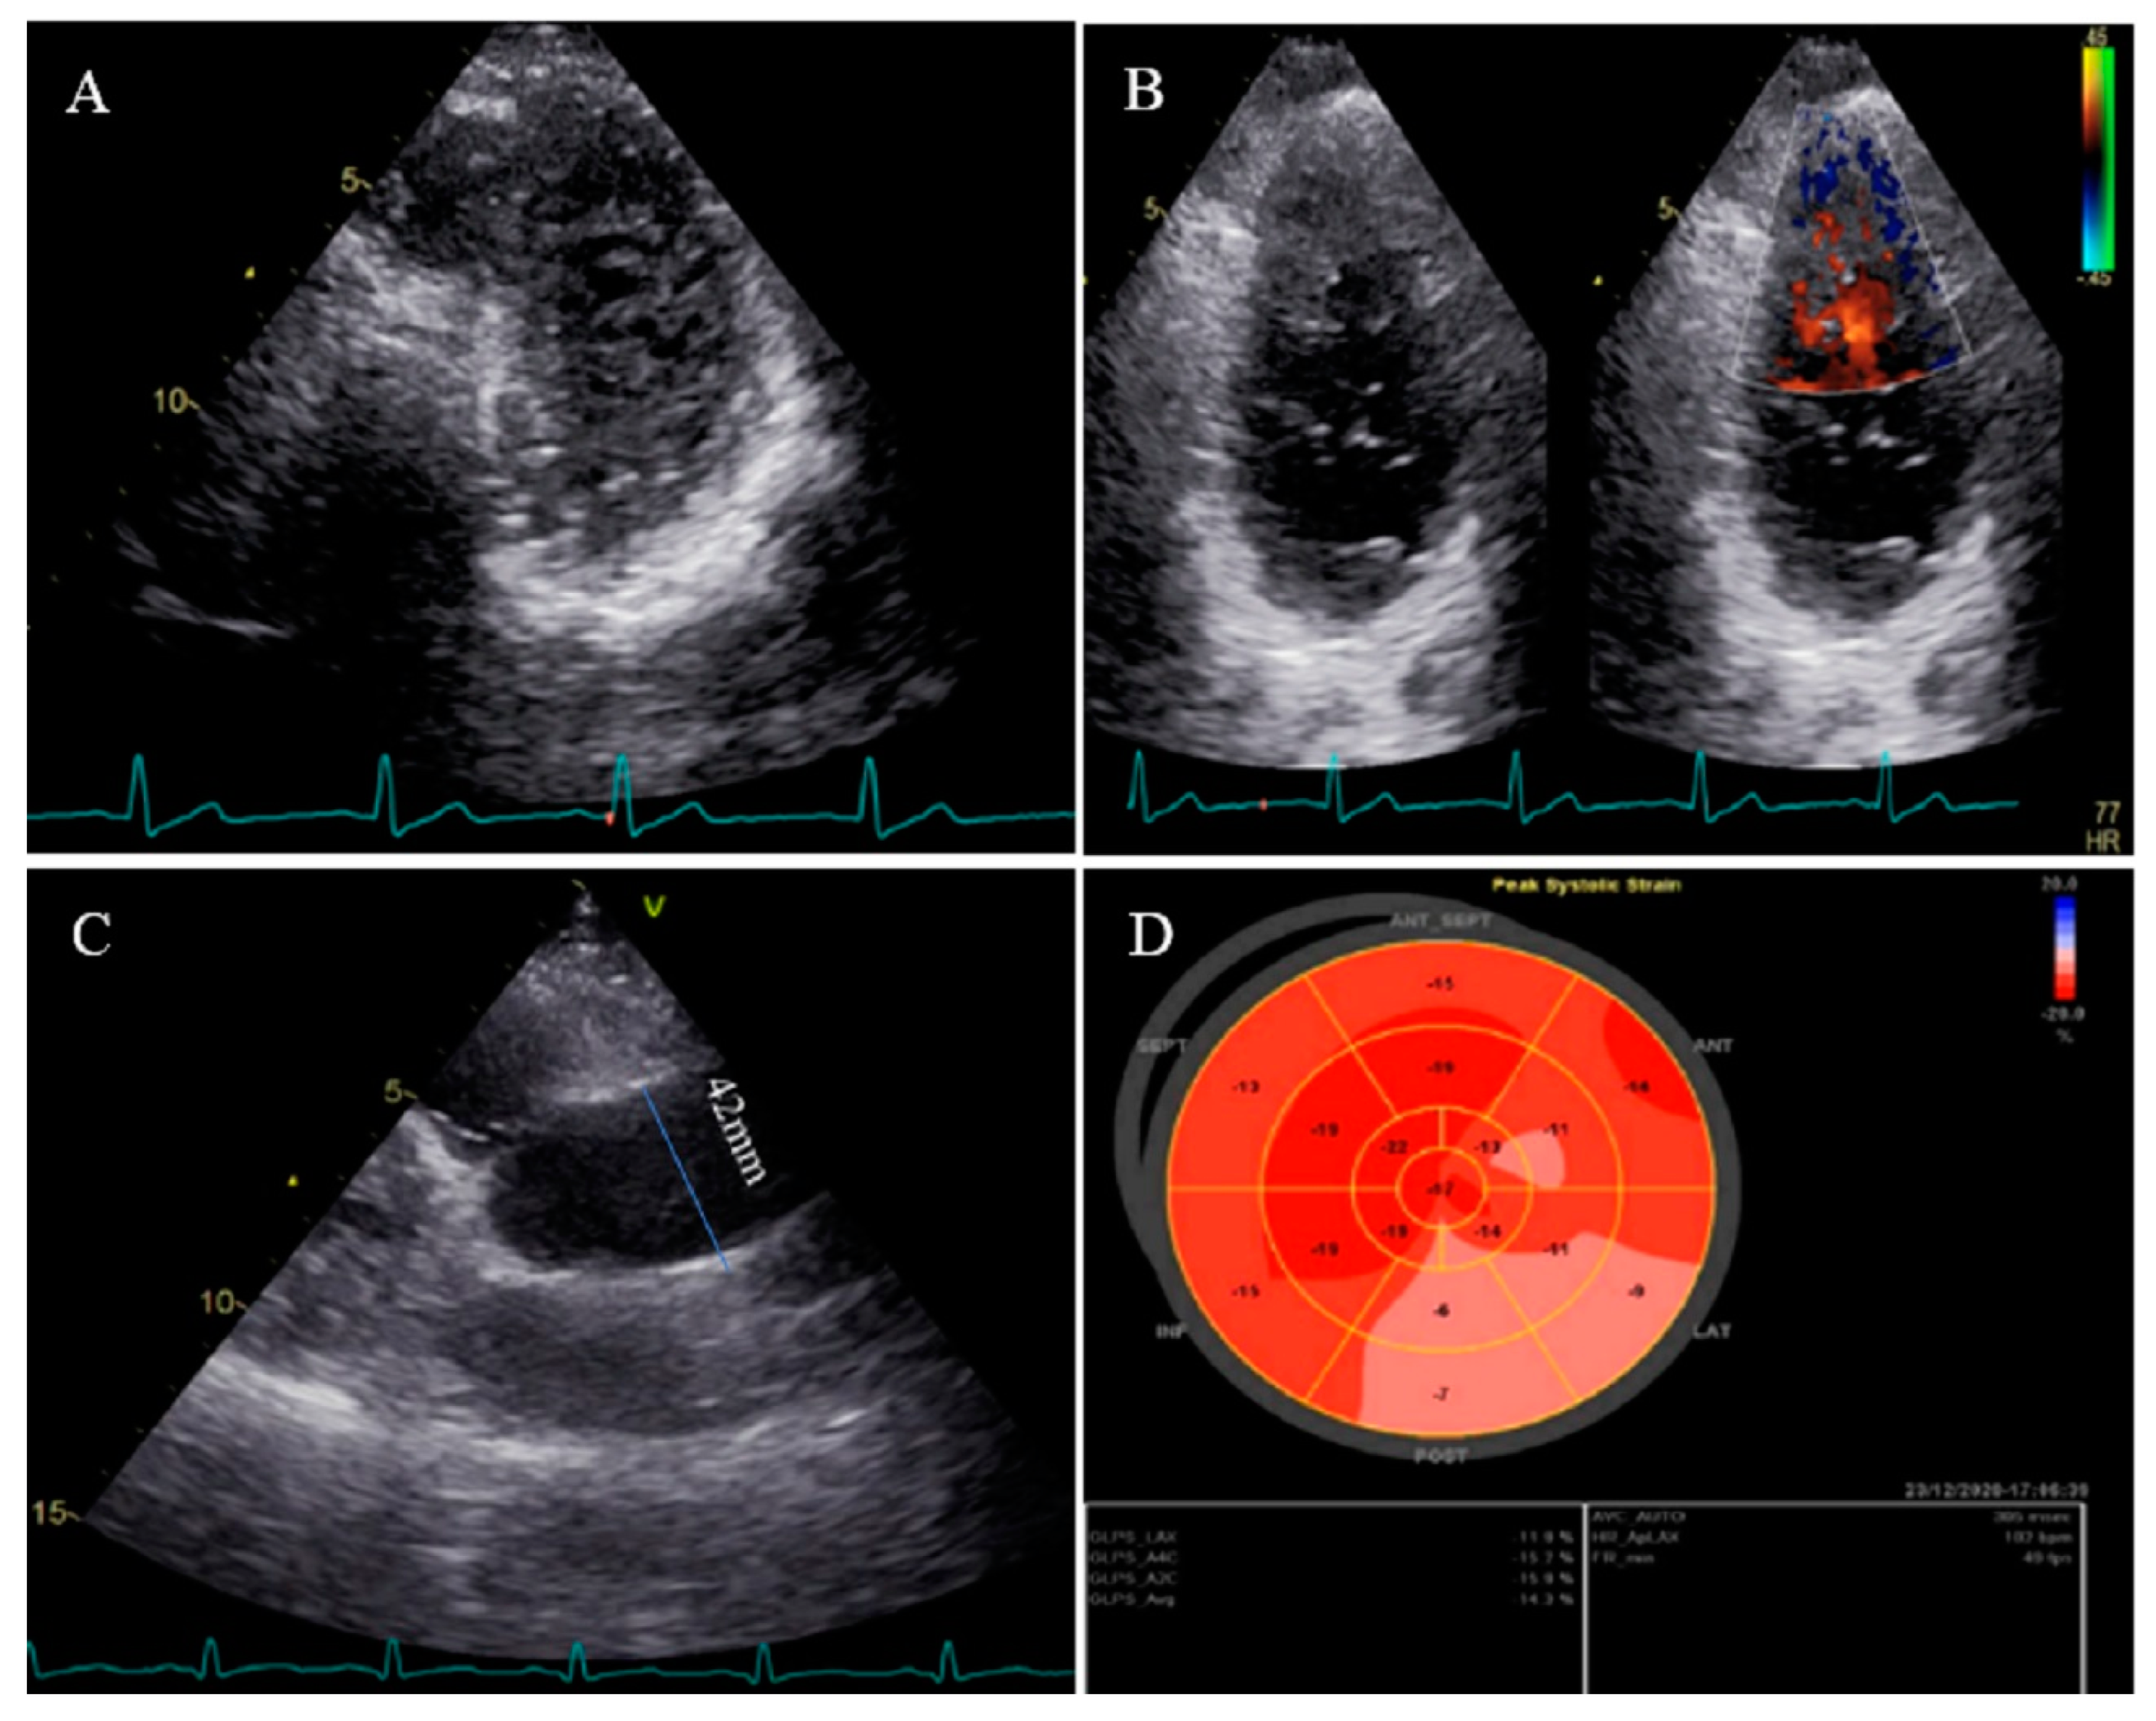

Figure 3.

Two-dimensional transthoracic echocardiographic views of case #3. (A); Left ventricular apical SAX view, illustrating hypertrabeculated apical portions in addition to deep intertrabecular recesses. (B); Color Doppler echocardiography, showing evidence of direct blood flow from the ventricular cavity into deep intertrabecular recesses. (C); Dilated aortic proximal ascending aorta. (D); Speckle tracking echocardiographic findings, compatible with myocardial performance impairment of all segments with GLS = −14.3%. (E,F); Coronary angiography showing on arrival and 2-week post-treatment results. (G); Cardiac magnetic resonance imaging, illustrating prominent non-compaction in left ventricular apical and lateral wall.

A 37-year-old gentleman with no history of cardiac disease and major CVD risk factors presented with acute retrosternal pain with radiation in both shoulders since 3 h prior to admission to the emergency department, accompanied by profound cold sweating and nausea, though there was no vomiting. On arrival, the ECG showed ST-segment elevation in the inferolateral leads, and diagnostic coronary angiography revealed a filling defect in the second obtuse marginal branch, in favor of occlusion by a fresh thrombus. He spent his hospital course uneventfully with response to anticoagulation plus dual antiplatelet therapy for 2 weeks (opened occlusion on the second angiography) and was discharged after 3 days in stable condition. Because of the possibility of the cardiac source of embolization, TTE and TEE were performed, which revealed NCLV with normal left ventricular ejection fraction (LVEF = 55%) and no obvious thrombus, in addition to mild aortic dilation (ascending aorta diameter = 42 mm; indexed = 22 mm). STE showed reduced global longitudinal strain (GLS = −11%). Moreover, CMR confirmed the diagnosis of NCLV (Figure 3). A genetic study showed two heterozygous mutations in the SCNIB and ALPK3 genes. The family screening was performed, and his mother had an undiagnosed isolated NCLV with the same genetic results, as well. The patient was prescribed warfarin and was symptom free at the follow-up visit.